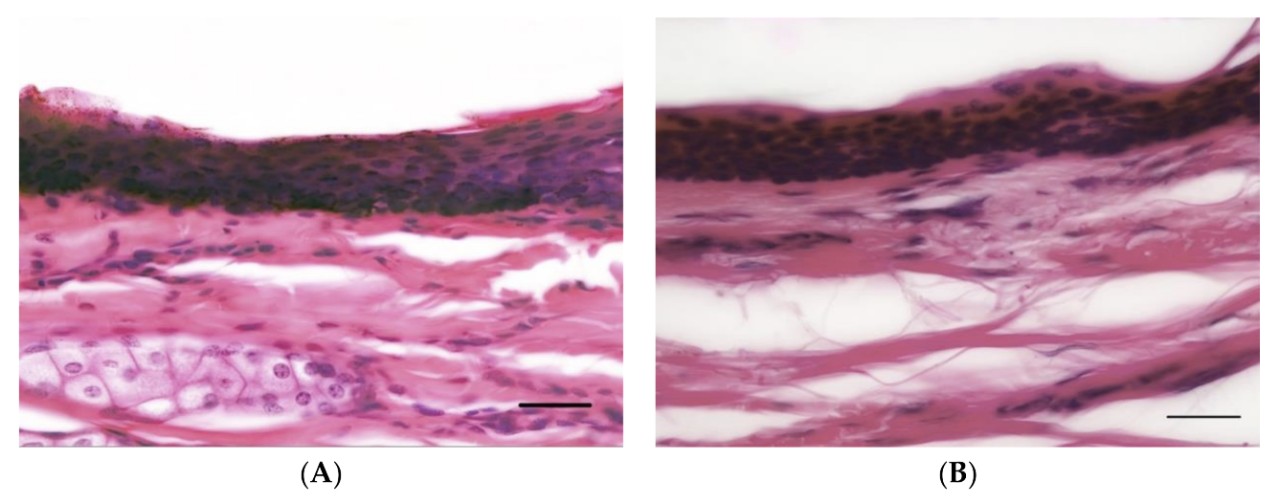

Close-ups of horse skin and human skin.

Images of horse (A) and human (B) skin, showing comparable epidermal thickness.

Professor McGreevy and colleagues examined whether horses are likely to feel as much pain as humans would when whipped. Using microscopic samples of skin from 10 deceased humans and 20 euthanised horses, they looked for differences between the species’ skin structure and nerve supply.

The results revealed “no significant difference” between humans and horses in the concentration of nerve endings in the outer layers of skin, nor any difference in thickness of this skin layer.